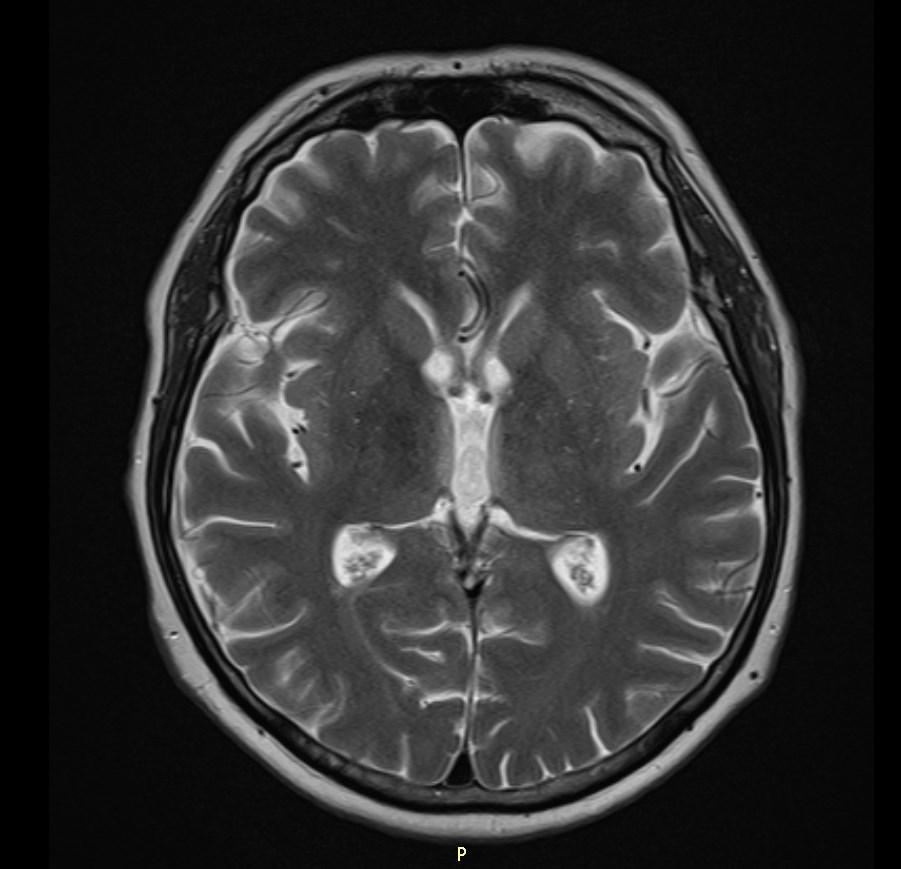

MRI images revealed hyperintensities in the periaqueductal region and the medial thalami.

T2/FLAIR: symmetrically increased signal intensity in the mamillary bodies, dorsomedial thalami, tectal plate, periaqueductal area, and around the third ventricle.